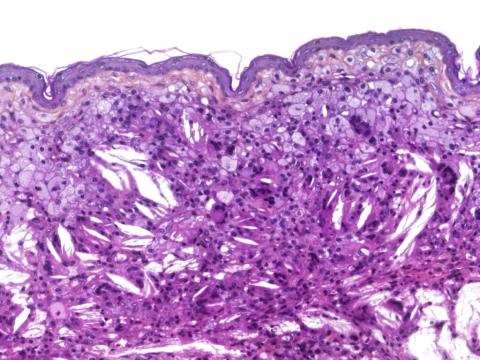

Histopathological findings: There is diffuse infiltration of the dermis by foamy macrophages and multinucleated giant cells, admixed with numerous cholesterol clefts.

Diagnosis: Cutaneous xanthoma

Comment: Xanthomas are common in psittacines (especially cockatiels and female budgerigars, as in this case). These inflammatory pseudotumors are typically composed of foamy macrophages, multinucleated giant cells and cholesterol clefts. They most commonly occur on the skin but can also be found in internal organs and in the bone marrow. Although the precise pathogenesis is still unknown, a disturbance in lipid metabolism is suspected.